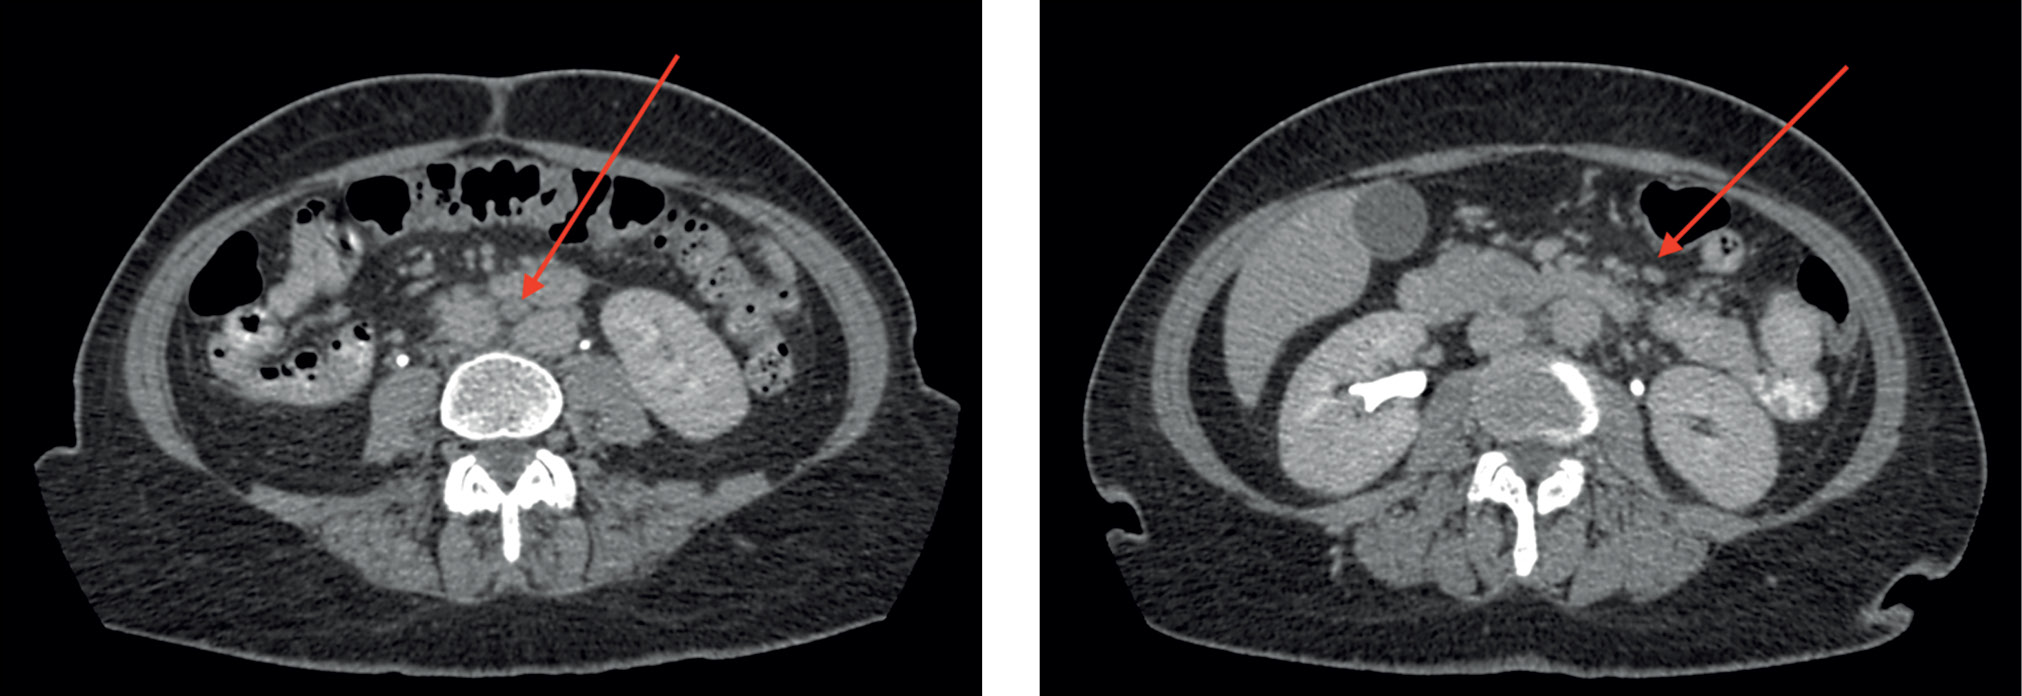

Upper gastrointestinal tract esophagogastroduodenoscopy revealed no abnormalities. A colonoscopy revealed erosive lesions of the descending colon, sigmoid, and rectum mucosa. The histology of the colon biopsy samples revealed catarrhal colitis. Abdominal CT with intravenous contrast (Figure 2) showed several abdominal lymph nodes (para-aortic and superior mesenteric lymph nodes, up to 10-mm short-axis diameter) during the patient’s stay in the Infection Department inpatient unit.

Fig. 2. Abdominal computed tomography scan with intravenous contrast (September 2020); axial plane: the red arrows show intraperitoneal lymph nodes.